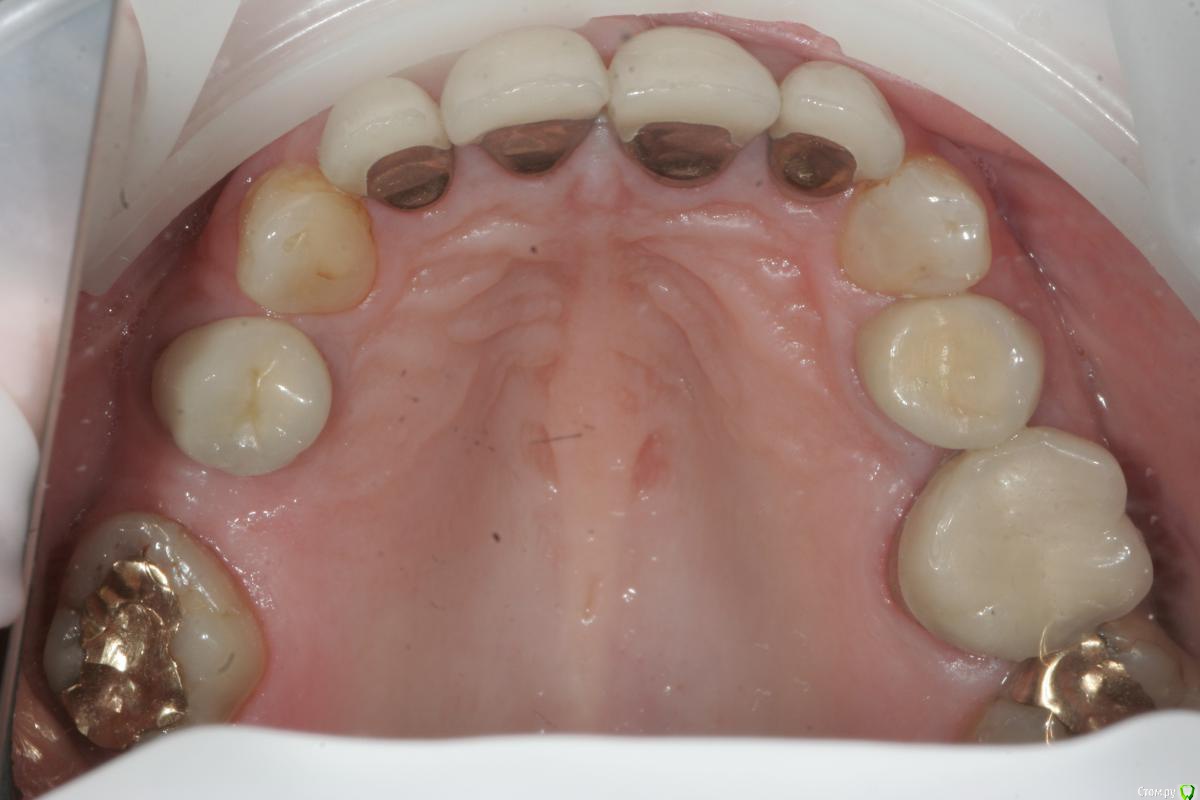

togrul Опубликовано 18 марта, 2015 Автор Поделиться Опубликовано 18 марта, 2015 Вот еще фото лица. По бюджету нет ограничений ( мк на золоте, Емах). Провести снятие, эндо, воск, временные, перио нужно , но хирург не планирует ( по определенным причинам). Если делать перио во фронте какая методика было бы наиболее оптимальным в данной ситуации?Начал снимать коронки им 20 лет, под ними все очень даже не плохо) высота нижнего отдела лица снижена на сколько пока не готов ответить. модели будут Ссылка на комментарий

togrul Опубликовано 6 сентября, 2015 Автор Поделиться Опубликовано 6 сентября, 2015 Я так понимаю что кейс завершен..хотелось бы услышать приведенный в исполнение план..хоть и фото мало,но по не у видно,что работа очень хороша..покрайней мере фронт выглядит симпотно..Даже разные зениты двоек придают индивидуальности и живость..хотя некоторые и не согласятся со мной и скорее всего взяли бы в руки скальпель Все верно кейс закончен)Мы согласовали вакс ап , перенесли в полость рта согласовали форму и размер передних зубов, не много переделали восковку. По силиконовым ключам отпрепарировали зубы и где то около 1,5 носили временные коронки и параллельно начали постоянную работу. Везде Емах одиночки, кроме 2 сегмента ,там поставили мост из 3 х ед. Место не было для имплантации + нужен был синус,подумали и решили сделать мост. Никакой хирургии не было только эндо.Фото будут Ссылка на комментарий

togrul Опубликовано 7 сентября, 2015 Автор Поделиться Опубликовано 7 сентября, 2015 А мост из какого материала??Из циркона побоялся делать из Емах, не смотря что промежуток была 1 ед. Ссылка на комментарий